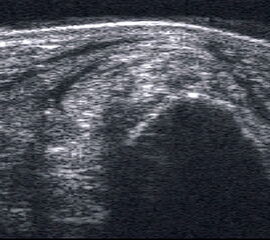

Peronealsehnenluxation

Peronealsehnenluxation. TS an der Fibulaspitze. Die Sehnen sind über die Fibula gerutscht.

Abbildung 45

Lagerung: Rückenlage, Innendrehung des Beins.

Schnittführung: TS und LS hinter dem Außenknöchel.

Referenzstrukturen: Fibulaspitze, Sehnen der Mm. peronaei.

Befunde: Halo-Phänomen. Bei der Luxation rutschen die Sehnen über den Außenknöchel nach lateral/ventral. Eine spontane Reposition unter Entspannung ist möglich. Im TS kann die Instabilität ggf. mittels Provokationstest durch Eversion gegen Widerstand sonographisch dynamisch dargestellt werden. Bei der Diagnostik der Peronealsehnen Instabilität oder Luxation ist die Sonographie durch die Möglichkeit der dynamischen Untersuchung dem MRT klar überlegen 4.